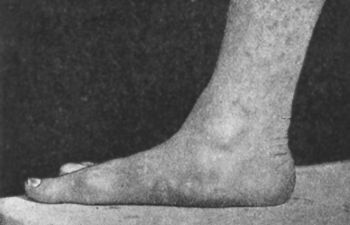

126.Tuberculous Disease of Right Ankle239